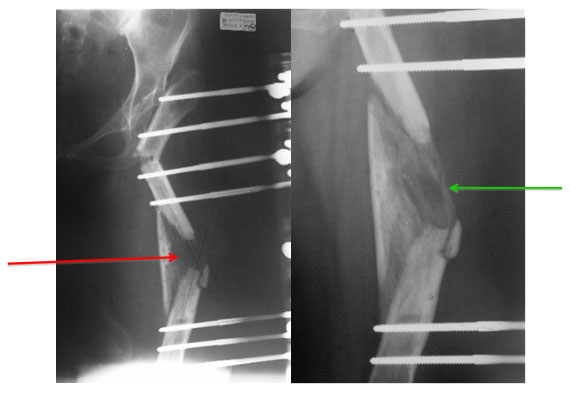

X-ray after surgery

The Ilizarov Hip Reconstruction consists of a double osteotomy. One at the level of ischial tuberosity giving support to the pelvis and one at distal level to correct the valgus deformity and shortening. Though the bone looks zigzag, the load bearing axis is centralized and the leg looks straight from outside. More importantly it takes care of the unsightly limp.

The xray on the left shows the distraction gap (red arrow) to compensate for the shortening. The x-ray on the right shows formation of new bone in the distraction gap (green arrow).